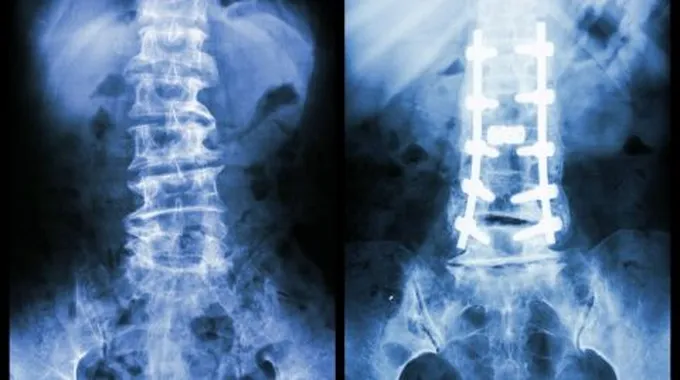

- إرجاع اجزاء العظم الى الوضع المقبول طبيا وتكون عملية الإرجاع اما بطرق مغلقة اوعن طريق تداخل جراحي

- تثبيت اجزاءالعظم في الوضع المقبول طبيا لحين التئام العظم وتكون عمليةالتثبيت اما عن طريق الجبائراوالمثبتات او اثقال متصلة بالطرف المصاب او عن طريق اجراء تداخل جراحي وتثبيت الكسر بواسطة الأسياخ او الصفائح المعدنية و خلال هذه الفترة يتم

التأهيل الطبيعي لمساعدة المصاب فيعودته لأداء وظيفته.